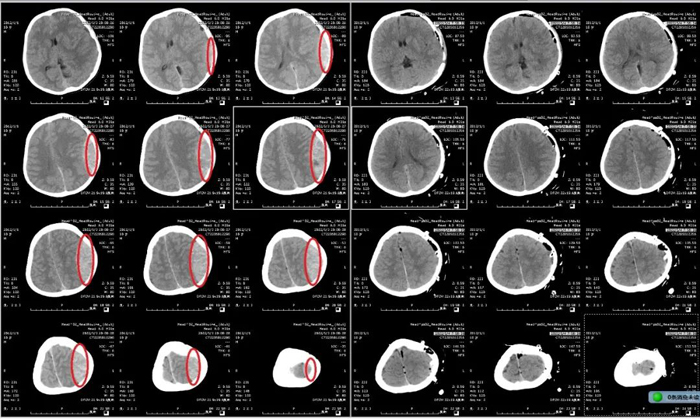

患兒,男,9歲,因“摔傷頭部后神志喪失1小時(shí)余”由120送到我院急診搶救室就診。入院時(shí)患兒昏迷、病危狀態(tài),不能言語(yǔ),一側(cè)瞳孔散大固定,伴一側(cè)肢體偏癱。急診顱腦CT檢查提示:左側(cè)巨大顱內(nèi)血腫,中線移位。急診神經(jīng)外科當(dāng)值醫(yī)師及上級(jí)醫(yī)師綜合評(píng)估病情后,決定立即啟動(dòng)急診綠色通道。

時(shí)間就是生命,對(duì)于神經(jīng)急危重癥患者,每一秒鐘對(duì)于整個(gè)疾病的搶救過(guò)程都彌足珍貴。呂守華主任接到電話后第一時(shí)間來(lái)到醫(yī)院,臨場(chǎng)組織搶救,指導(dǎo)手術(shù)。手術(shù)者蓋大偉主治醫(yī)師以精湛的技術(shù)用時(shí)100分鐘順利完成手術(shù),術(shù)后復(fù)查示顱內(nèi)血腫清除滿意。

顱腦CT術(shù)前、術(shù)后對(duì)比

術(shù)后,患兒轉(zhuǎn)入神經(jīng)重癥監(jiān)護(hù)室對(duì)癥治療、專業(yè)護(hù)理。因患兒年齡小、心理恐懼,科室護(hù)理團(tuán)隊(duì)像媽媽一樣無(wú)微不至地照顧、安撫、鼓勵(lì)患兒。經(jīng)過(guò)醫(yī)護(hù)團(tuán)隊(duì)悉心的照料,患兒次日便順利脫掉呼吸機(jī)、拔除氣管插管。轉(zhuǎn)入普通病房前,患兒意識(shí)清醒,言語(yǔ)對(duì)答清楚,肢體活動(dòng)正常?;純涸诩覍俚呐阃拢H手將錦旗送到李肖穎護(hù)士長(zhǎng)手中。(神經(jīng)重癥監(jiān)護(hù)室) ?